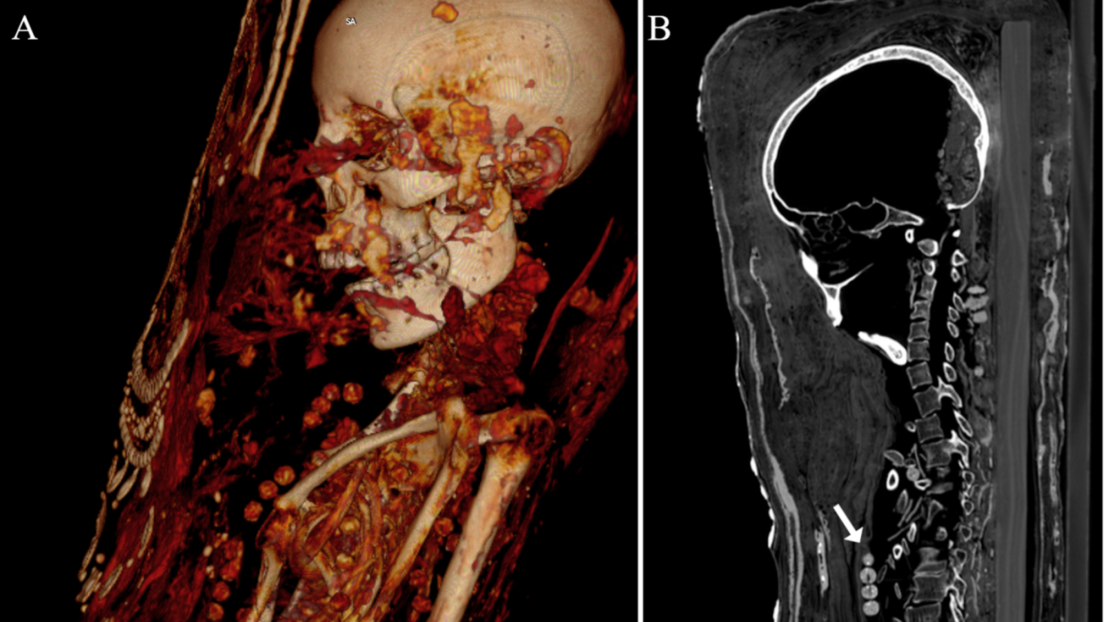

Mediante análisis de tomografía computerizada, lograron obtener información sobre el estado de conservación de los cuerpos, la técnica usada , la edad de los individuos en el momento de la muerte, así como su género, altura y salud.

"Investigaciones radiológicas revelaron que algunas no mostraban evidencia de extirpación del cerebro y de los intestinos”, dijo Stephanie Zesch, investigador principal del estudio.

Los expertos indicaron que la momificación de estos tres cadáveres fue diferente a como lo hacían anteriormente ya que antes les extirpaban los órganos y en este caso los cuerpos fueron colocados sobre tablas de madera antes de ser envueltos en tela, yeso y oro, añadiendo en la superficie un retrato de cuerpo entero.